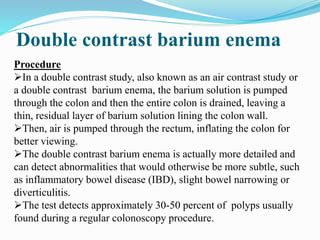

This document discusses colorectal polyps. It defines polyps and describes their types, including neoplastic and non-neoplastic polyps. It discusses adenomatous polyps in depth, noting their malignant potential increases with size over 1cm and villous architecture. Radiological diagnostic methods for polyps including single and double contrast barium enema and CT colonography are explained. The document provides an overview of polyp pathogenesis and genetic syndromes like FAP that increase cancer risk.